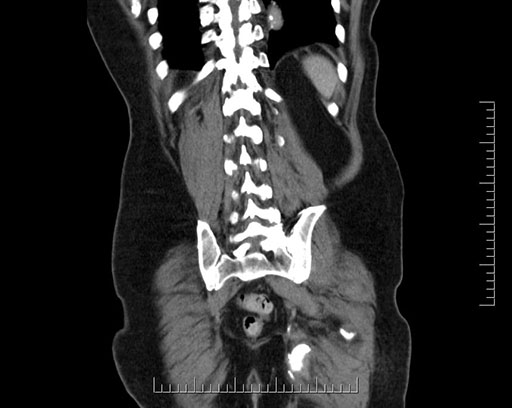

Coronal - stented